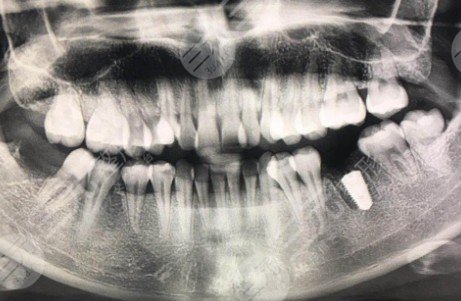

已经是半个月前面诊了,因为工作时间的关系,我没去手术。今天,我终于来做手术了,做新的种植体。我在医院的护士们很温柔,医院的环境相当好,有很多人来看病。因为之前在做抽血洗牙,吃了术后止痛药之后进了手术的房间。在手术的整个旅程大约需要40分钟。过程中没有明X感觉,很快就结束了。等了半个小时后,医生看了看伤口,确认没有问题。让七天将来来拆线,希望早日康复。

昨天,我去了拆线,医院,没有在几分钟内感受到拆线,和医生的整个过程没过去一分钟,然后我就可以走了。这款牙齿脱线后感觉舒服多了,没有了之前一直感觉到的线的摩擦力。事实上,现在,没有什么特别的,伤口也很好,只是在等待牙龈和种植成长到稳定的状态后再去加冠。当现在的舌头碰到那个地方的时候,他不时会觉得少了一坨,然后还有一点点不适应,但是时间越长,就应该完全适应了。医生说需要三个月。个人觉得吃一些特色菜不太方便。